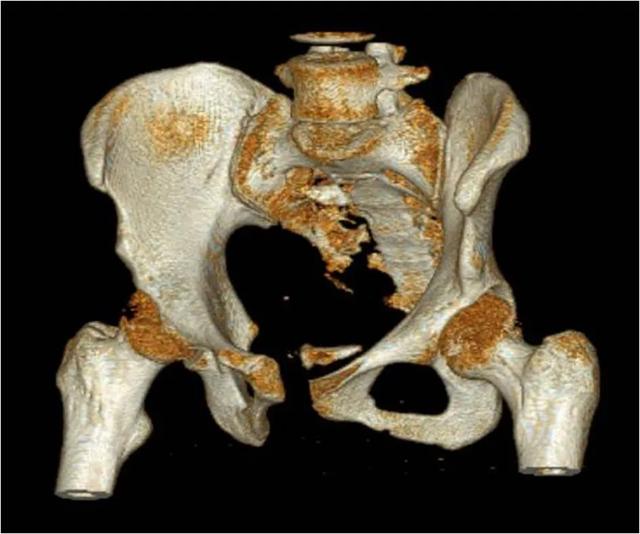

大きな外傷(脊椎の多発乾燥骨折骨盤)

また、整形外科では、より外傷性の高い手術も行われる。颈椎手術の骨盤骨折手術などの

頸椎の重要性は誰もが知っているが、骨盤についてはあまり知られていないかもしれない。骨盤骨折からの出血は特に多い。場合によっては、出血性ショックにつながり、生命を脅かすこともある。 したがって、整形外科医は、大きな外傷の手術を行う前に、必ず患者を系統的に評価すると同時に、手術中に出血が起こる可能性に対処できるよう、血液をスタンバイしておく必要がある。

- 小遣い骨組織は血行性に富み、特に骨切片、骨髄腔、脊柱管内では、一般に出血量が多く、出血のコントロールが困難である。以下のような侵襲性の高い手技もある。股関節全置換術、脊椎手術、骨盤手術では出血が多くなる.術中の出血量が多い場合、出血性ショックが起こることがある。術中輸血は可能であるが、心肺機能が低下している高齢者にとっては、大量出血は身体的に耐え難いものである。